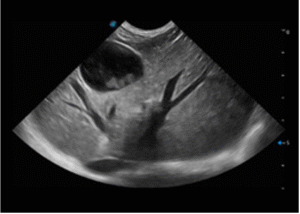

• Reproduction & Breeding

Ultrasound is essential for pregnancy confirmation, fetal viability assessment, and reproductive disease evaluation, making it a high-frequency tool in both breeding clinics and general hospitals.